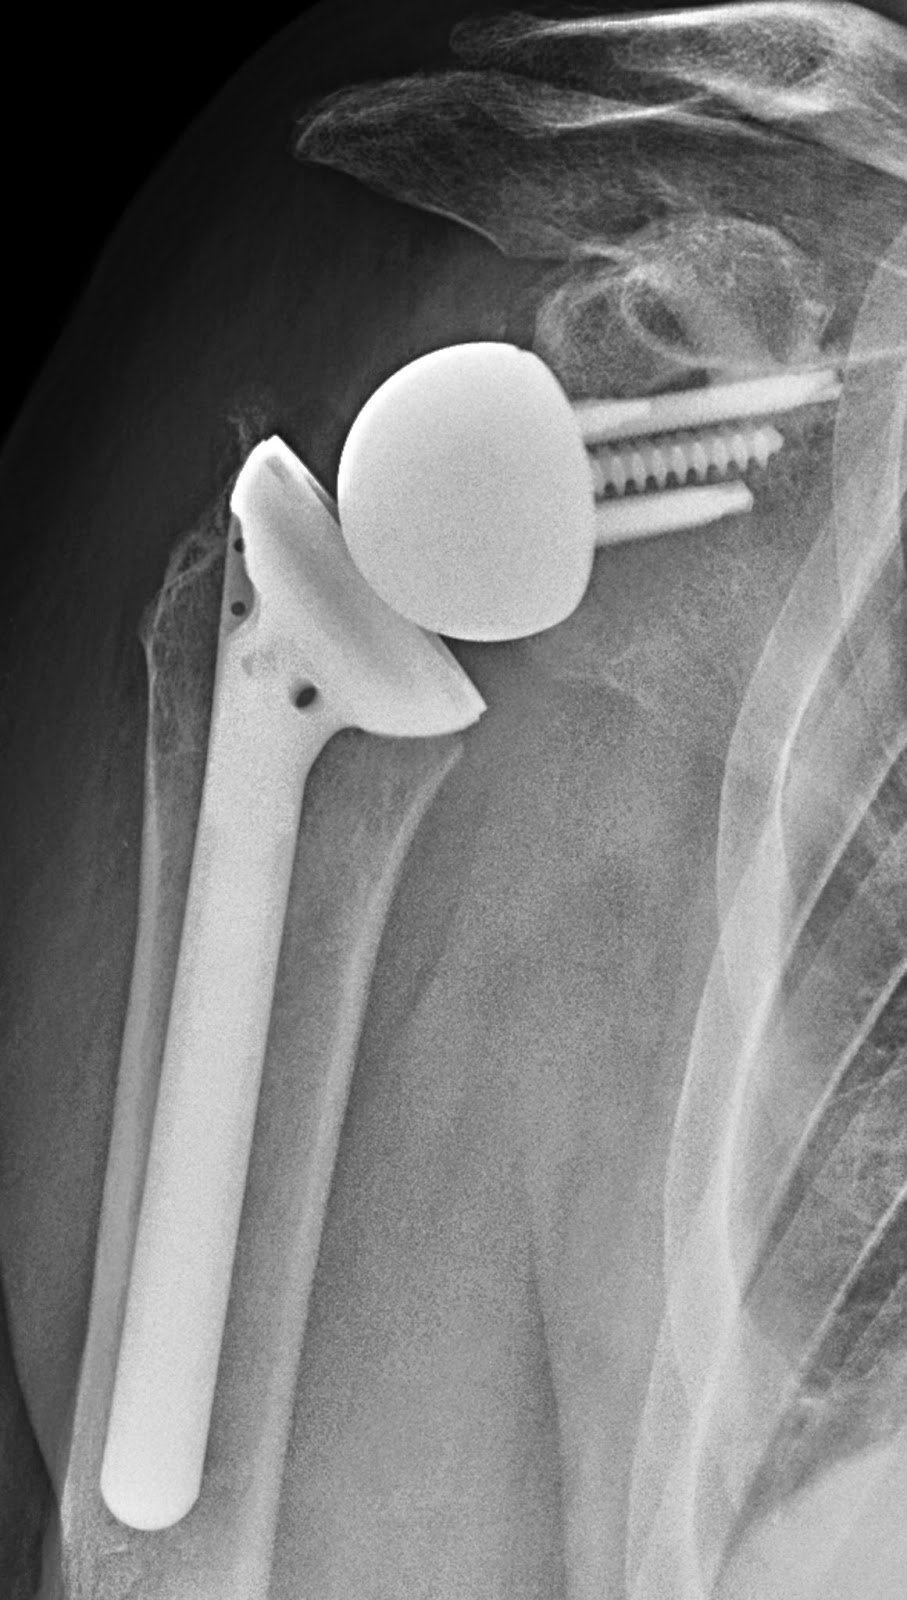

Reverse Total Shoulder Prosthesis

تصميم كرة ومقبس معكوس (كرة حقانية + كأس عضدية) لاعتلال مفصل الكفة المدورة والتمزقات الضخمة غير القابلة للإصلاح.

مفصل الكتف العكسي الكلي (RTSP)، والذي يشار إليه غالبًا باسم استبدال الكتف العكسي، هو نوع متخصص من جراحة استبدال مفصل الكتف (الرأب المفصلي). على عكس استبدال الكتف الكلي التقليدي حيث يتم محاكاة التشريح الطبيعي (الكرة على عظم العضد، التجويف على لوح الكتف)، فإن RTSP يعكس هذا التكوين حرفيًا. في الاستبدال العكسي، يتم تثبيت كرة معدنية (الكرة الحقانية) على لوح الكتف، ويتم ربط تجويف بلاستيكي (الكأس العضدي) بعظم الذراع العلوي (العضد).

1. الكرة الحقانية (Glenosphere): هذا هو المكون الكروي المعدني الذي يتم تثبيته على التجويف الحقاني (الوعاء) للوح الكتف. عادة ما يكون مصنوعًا من سبيكة الكوبالت والكروم المصقولة جيدًا، والمعروفة بقوتها ومقاومتها للتآكل.

2. لوحة القاعدة الحقانية (Glenoid Baseplate): عادة ما يتم تثبيت لوحة قاعدة من التيتانيوم على لوح الكتف بمسامير. ثم يتم ربط الكرة الحقانية بهذه اللوحة. يفضل التيتانيوم لتوافقه الحيوي الممتاز وقدرته على الاندماج مع العظام (الاندماج العظمي).

3. الجذع العضدي (Humeral Stem): يتم إدخال هذا المكون في القناة النخاعية (تجويف النخاع) لعظم العضد (عظم الذراع العلوي). عادة ما يكون مصنوعًا من التيتانيوم أو الكوبالت والكروم. يوفر الجذع الثبات ومنصة للكأس العضدي.

4. الكأس العضدي (Humeral Cup): هذا هو المكون البلاستيكي (البولي إيثيلين) الذي يتصل بالكرة الحقانية. عادة ما يكون مصنوعًا من البولي إيثيلين عالي الوزن الجزيئي للغاية (UHMWPE)، وهي مادة مختارة لاحتكاكها المنخفض ومقاومتها للتآكل وتوافقها الحيوي الممتاز.

5. الصينية العضدية (Humeral Tray): غالبًا ما يجلس الكأس العضدي داخل صينية عضدية معدنية، عادة ما تكون مصنوعة من التيتانيوم أو الكوبالت والكروم، والتي يتم تثبيتها بعد ذلك بالجذع العضدي.